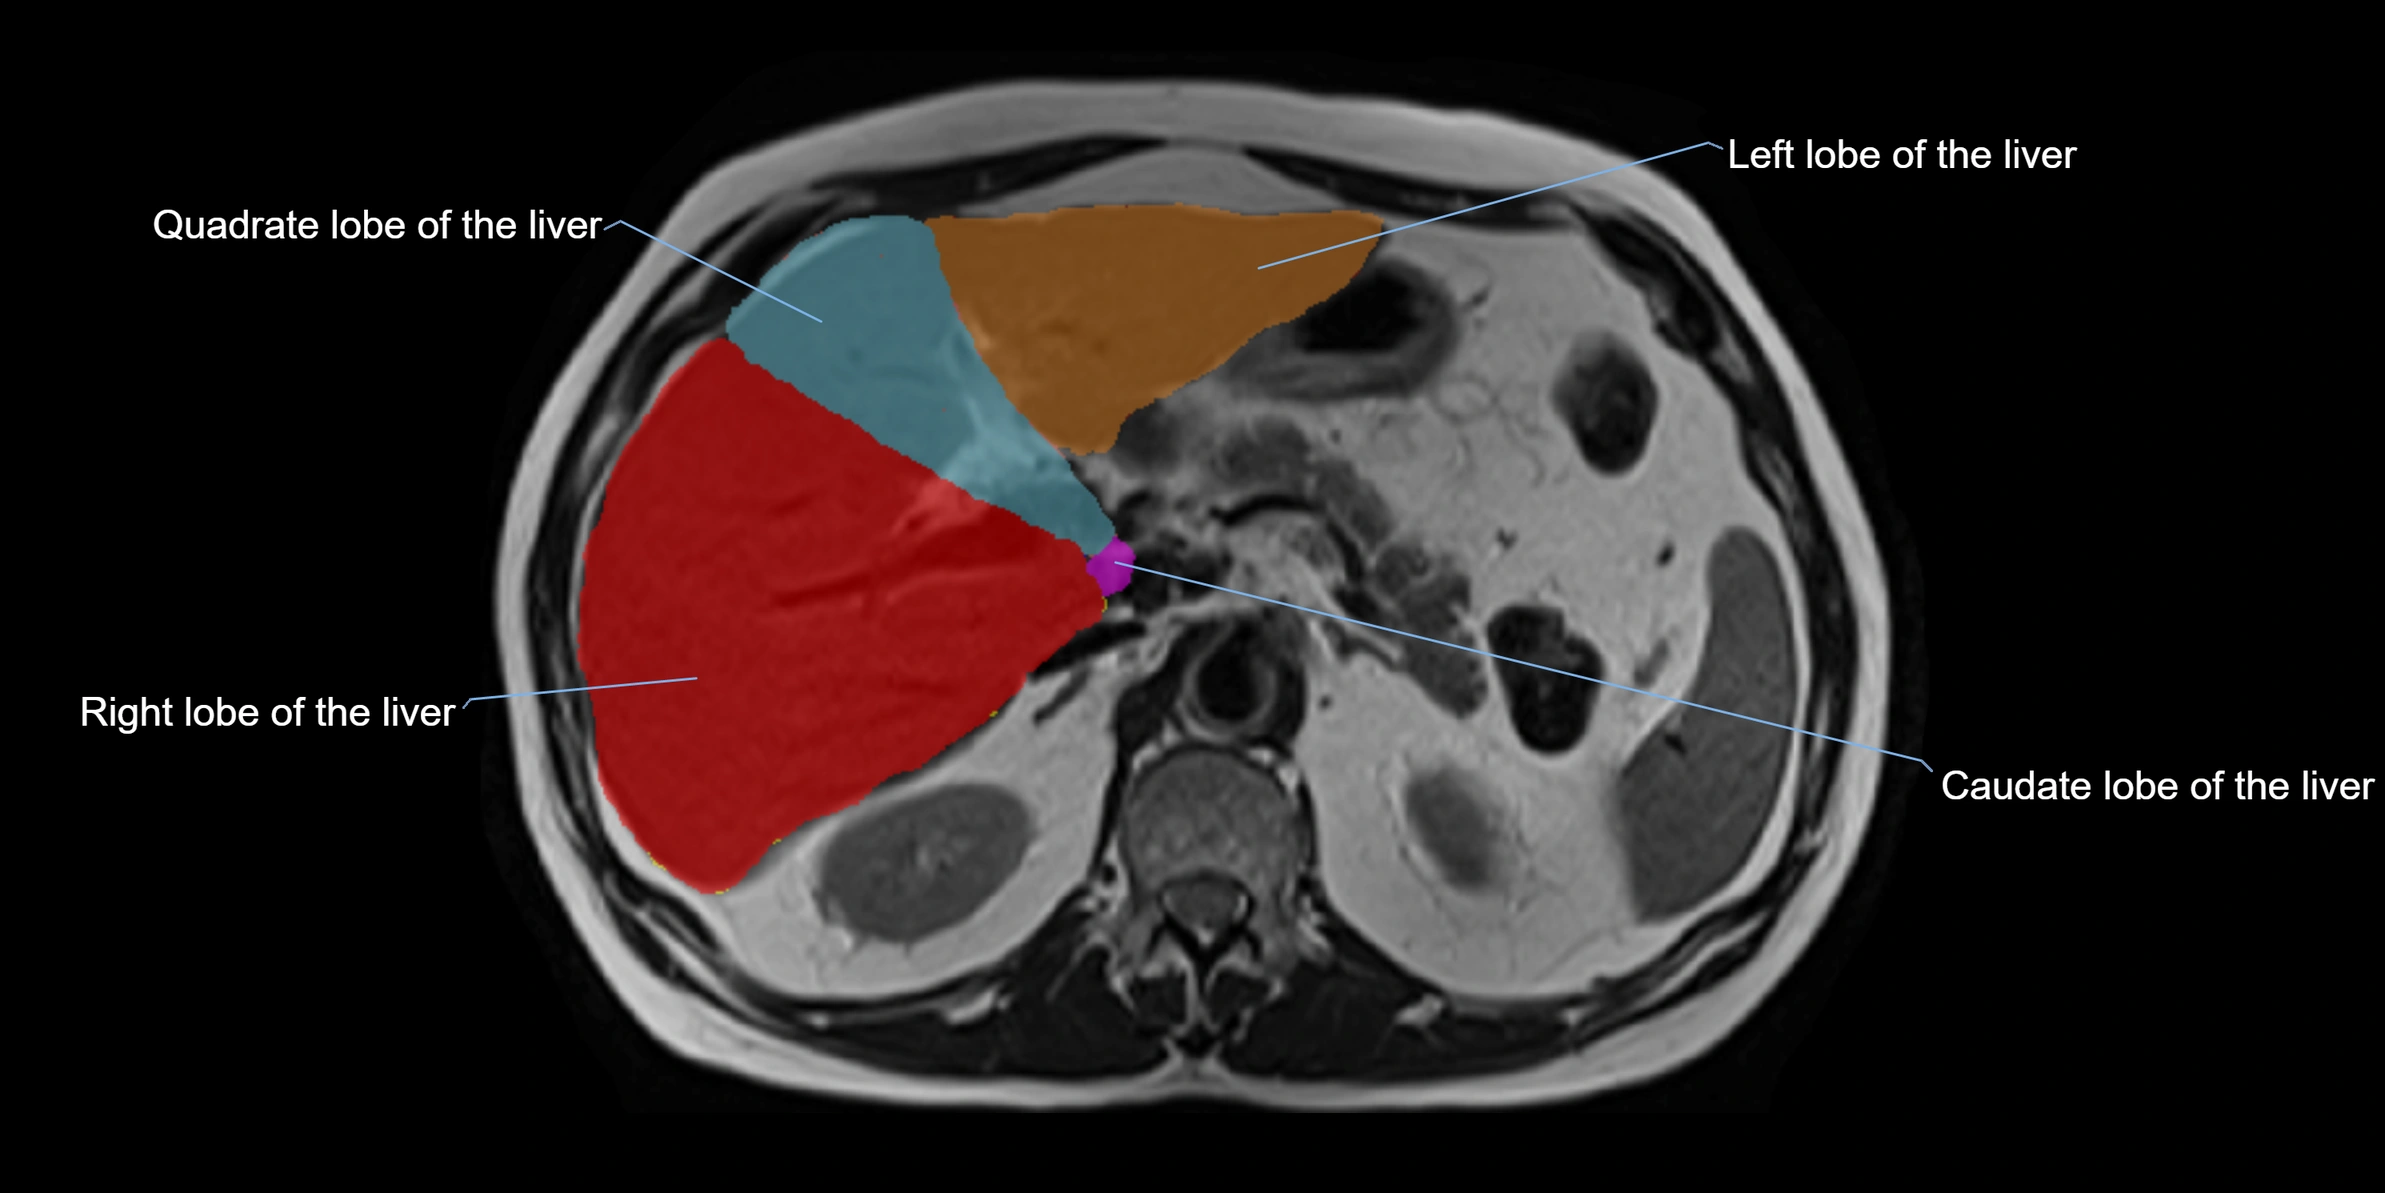

The caudate lobe of the liver is a distinct anatomical subdivision of the liver, designated as segment I in Couinaud’s classification. It lies on the posterior surface of the liver, between the fissure for the ligamentum venosum (left boundary) and the groove for the inferior vena cava (IVC) (right boundary). Superiorly, it is related to the posterior liver surface, and inferiorly it is separated from the left lobe by the porta hepatis.